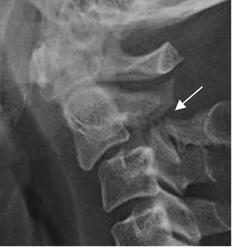

La Rx puede ser normal, por la reducción inmediata después del impacto. El ensanchamiento de la parte anterior del espacio intervertebral y la disminución del posterior, con prominencia de tejidos blandos, debe hacer sospechar esta lesión. (41). (Fig 201 A).

La avulsión asociada debe diferenciarse de fractura en lágrima, donde el fragmento suelto tiene mayor diámetro transverso, que vertical. (41). (Fig 201 B).

Fig 201 B. Fractura por hiperextensión.

Rx lateral. Fractura en la parte anterior del cuerpo, con fragmento mas ancho, que alto.